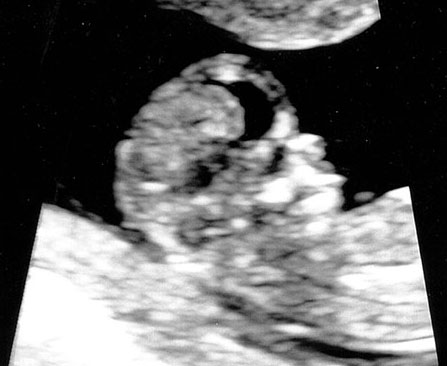

It all started with a …

With many recent expenditures, we’ve decided to put an embargo on eating out. This meant more time relaxing at home and a glut of TV watching. Season 5 of Game of Thrones was another engaging thrill ride, although the finale proved once again that no one is safe. To lighten things up, we decided to shift over to watching sitcoms, including Netflix’s incredible Unbreakable Kimmy Schmidt, which reminded us of Tina Fey humor and New York quirkiness, as well as CBS’ Big Bang Theory. Already in its 8th season, the show brilliantly touches on a spectrum of neuroses and eccentricities that are so pervasive and characteristically ingrained in the science and nerd-geek community. And while Melody was keeping step with new seasons of SYTYCD and ABDC, I began working on the new vacation album. The mindless task and dual-screen displays allowed me to clear out part of our movie queue, though none were very memorable. We did score a free screening of Mission Impossible: Rogue Nation from our BMW dealership which was surprisingly decent and entertaining. But perhaps our greatest excitement this summer is the arrival of a new beginning, which we hope is the start of a new adventure for us. We made the official announcement to our parents this weekend, and already my mom has added us to her Costco membership. Our life is about to change, and after many years, we feel finally ready.